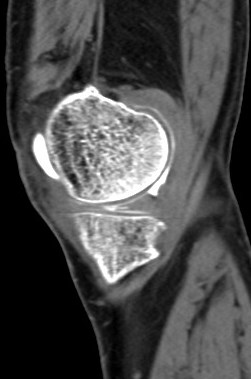

68 yo male with medial knee pain and a pacemaker.

Figure 4 for case Medial meniscus tear ( RID2772 )

Figure 4

Oblique tear of the medial meniscus shown on a CT arthrogram.

Medial meniscus tear ( RID2772 )